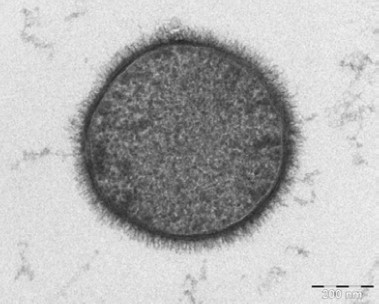

Alla eukaryota celler (celler med kärna) har en ”hårig” yta bestående av kraftigt glykosylerade proteiner, sockerarter och lipider. Denna håriga yta har flera funktioner, bland annat att reglera cellsignalering och utgöra ett skydd mot att oönskade molekyler ska kunna ta sig in till cellmembranet och ta sig igenom dess mellanliggande öppningar. Denna håriga struktur kallas endotel glykokalyx, och visas i detalj på bilden ovan.